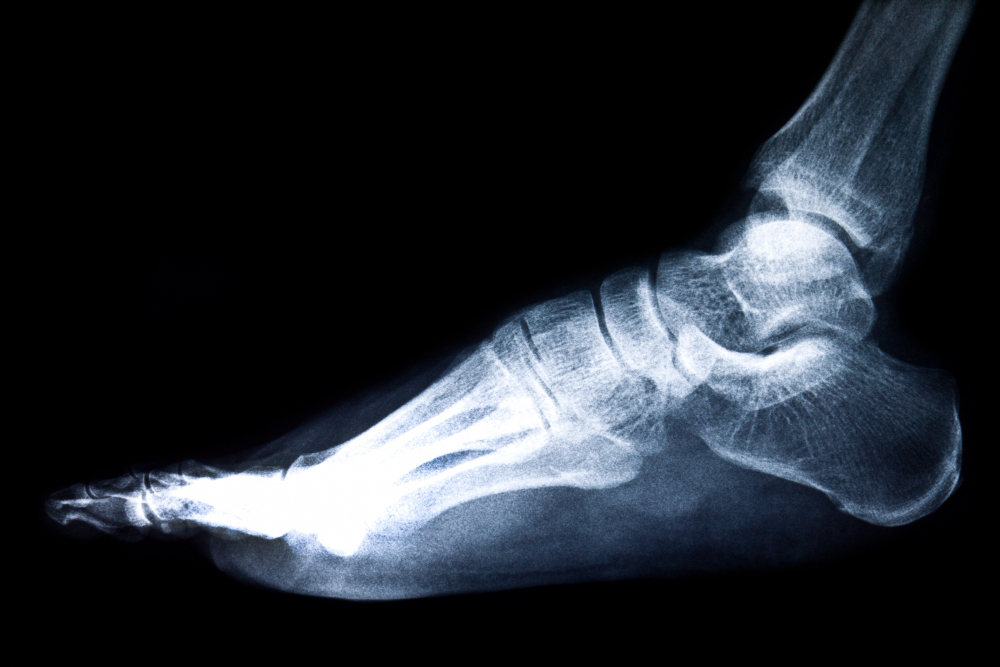

La artroplastía de tobillo es un procedimiento quirúrgico destinado a reemplazar la articulación del tobillo dañada con una prótesis artificial, permitiendo una mayor movilidad y reduciendo el dolor. El Dr. Francisco Castillo Vazquez utiliza técnicas avanzadas y prótesis de alta calidad para asegurar una recuperación efectiva y una mejor calidad de vida para sus pacientes.

La artroplastía de tobillo implica el reemplazo de la articulación del tobillo dañada por una prótesis artificial, permitiendo una mayor movilidad y reduciendo el dolor. Este procedimiento es recomendado para pacientes con artritis severa o daño significativo en el tobillo que no responden a tratamientos conservadores.